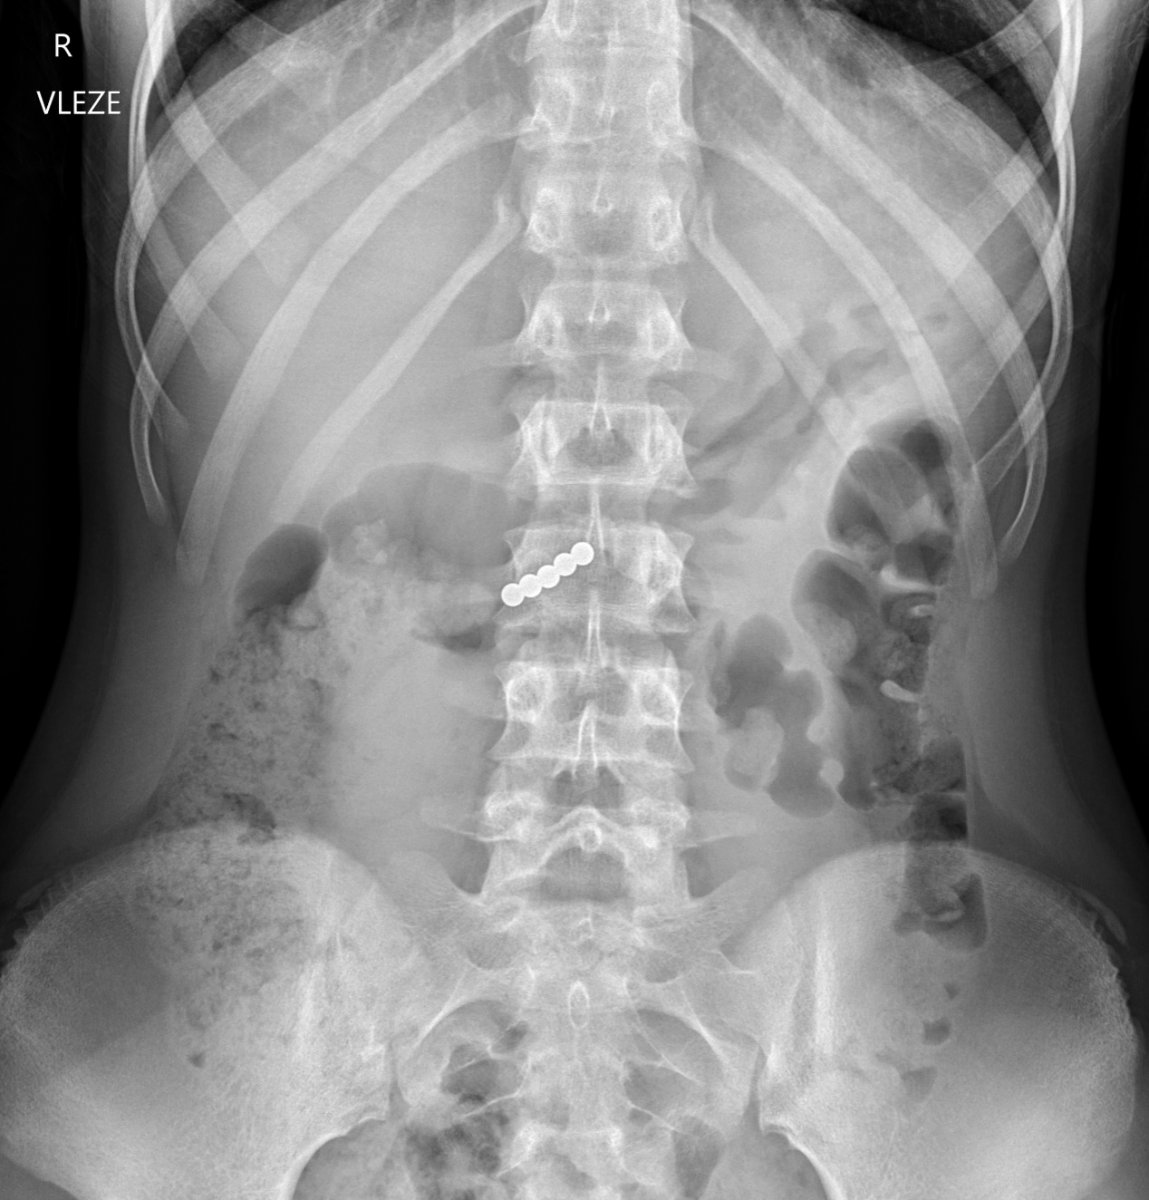

Galéria k článku Rodičia, POZOR! Šíri sa NEBEZPEČNÝ TikTok trend: Viacero detí skončilo v nemocnici

Zdroj: FN Motol